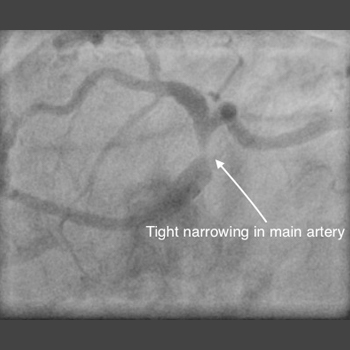

Chronic Total occlusion (CTO) angioplasty

Chronic Total occlusion…

Learn more